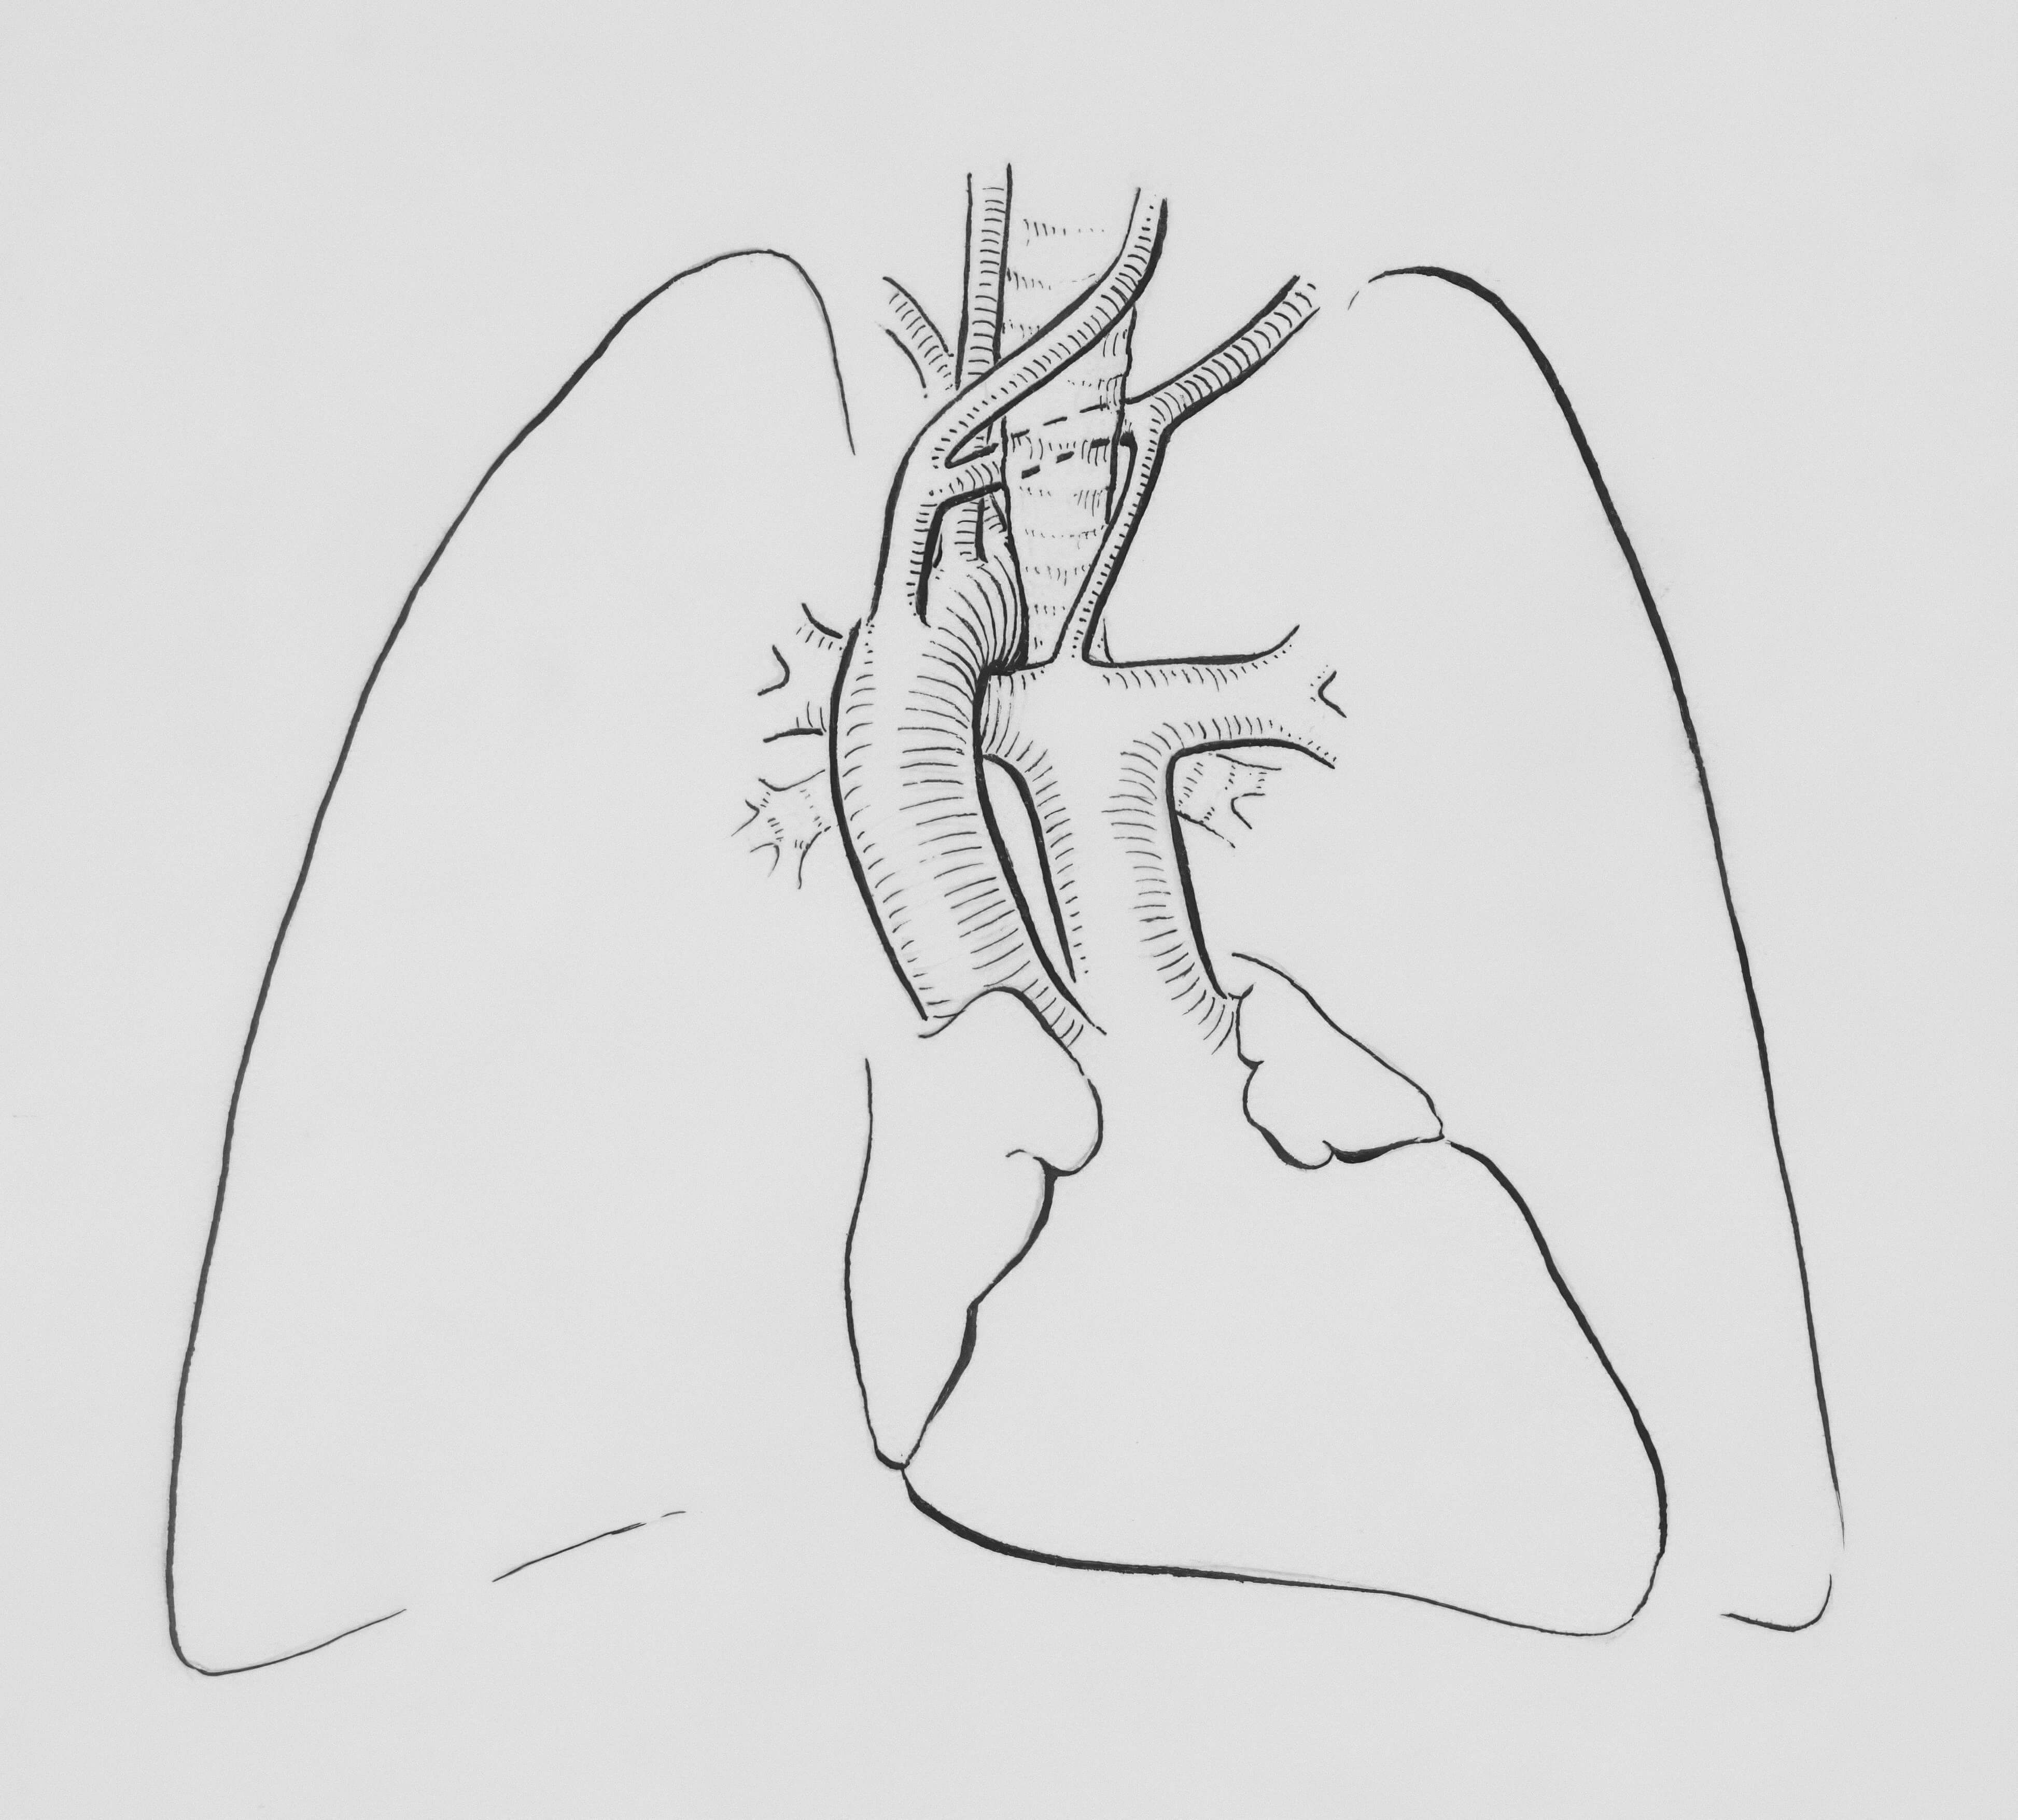

폐기흉(공기가슴증)은 폐의 표면에 구멍이 생겨 늑막강(가슴막 사이의 공간)에 공기가 들어가면서 폐가 쭈그러드는 질환입니다. 특히 키가 크고 마른 젊은 남성에게 자주 발생하며, 적절한 치료를 받지 않으면 생명에 위험할 수 있습니다.

건강한 사람의 늑막강은 음압을 유지하여 폐가 팽창된 상태를 유지하는데, 기흉이 발생하면 이 균형이 깨져 폐가 수축하게 됩니다.

- 흉강경 수술

- 최소 침습 수술

- 기포 제거 및 유착술